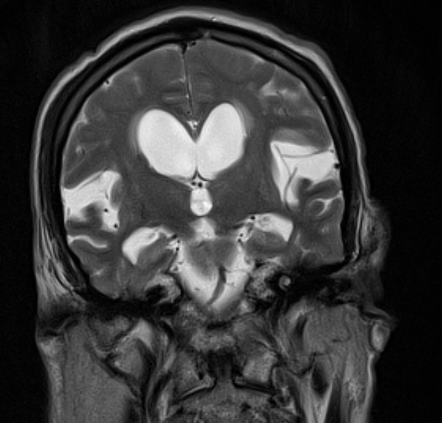

- Neuroimaging: Crucial for diagnosis.

- MRI: Shows characteristic, often asymmetric, atrophy in the frontal and/or temporal lobes.

- Neuroimaging reveals focal atrophy of the frontal and/or temporal lobes.